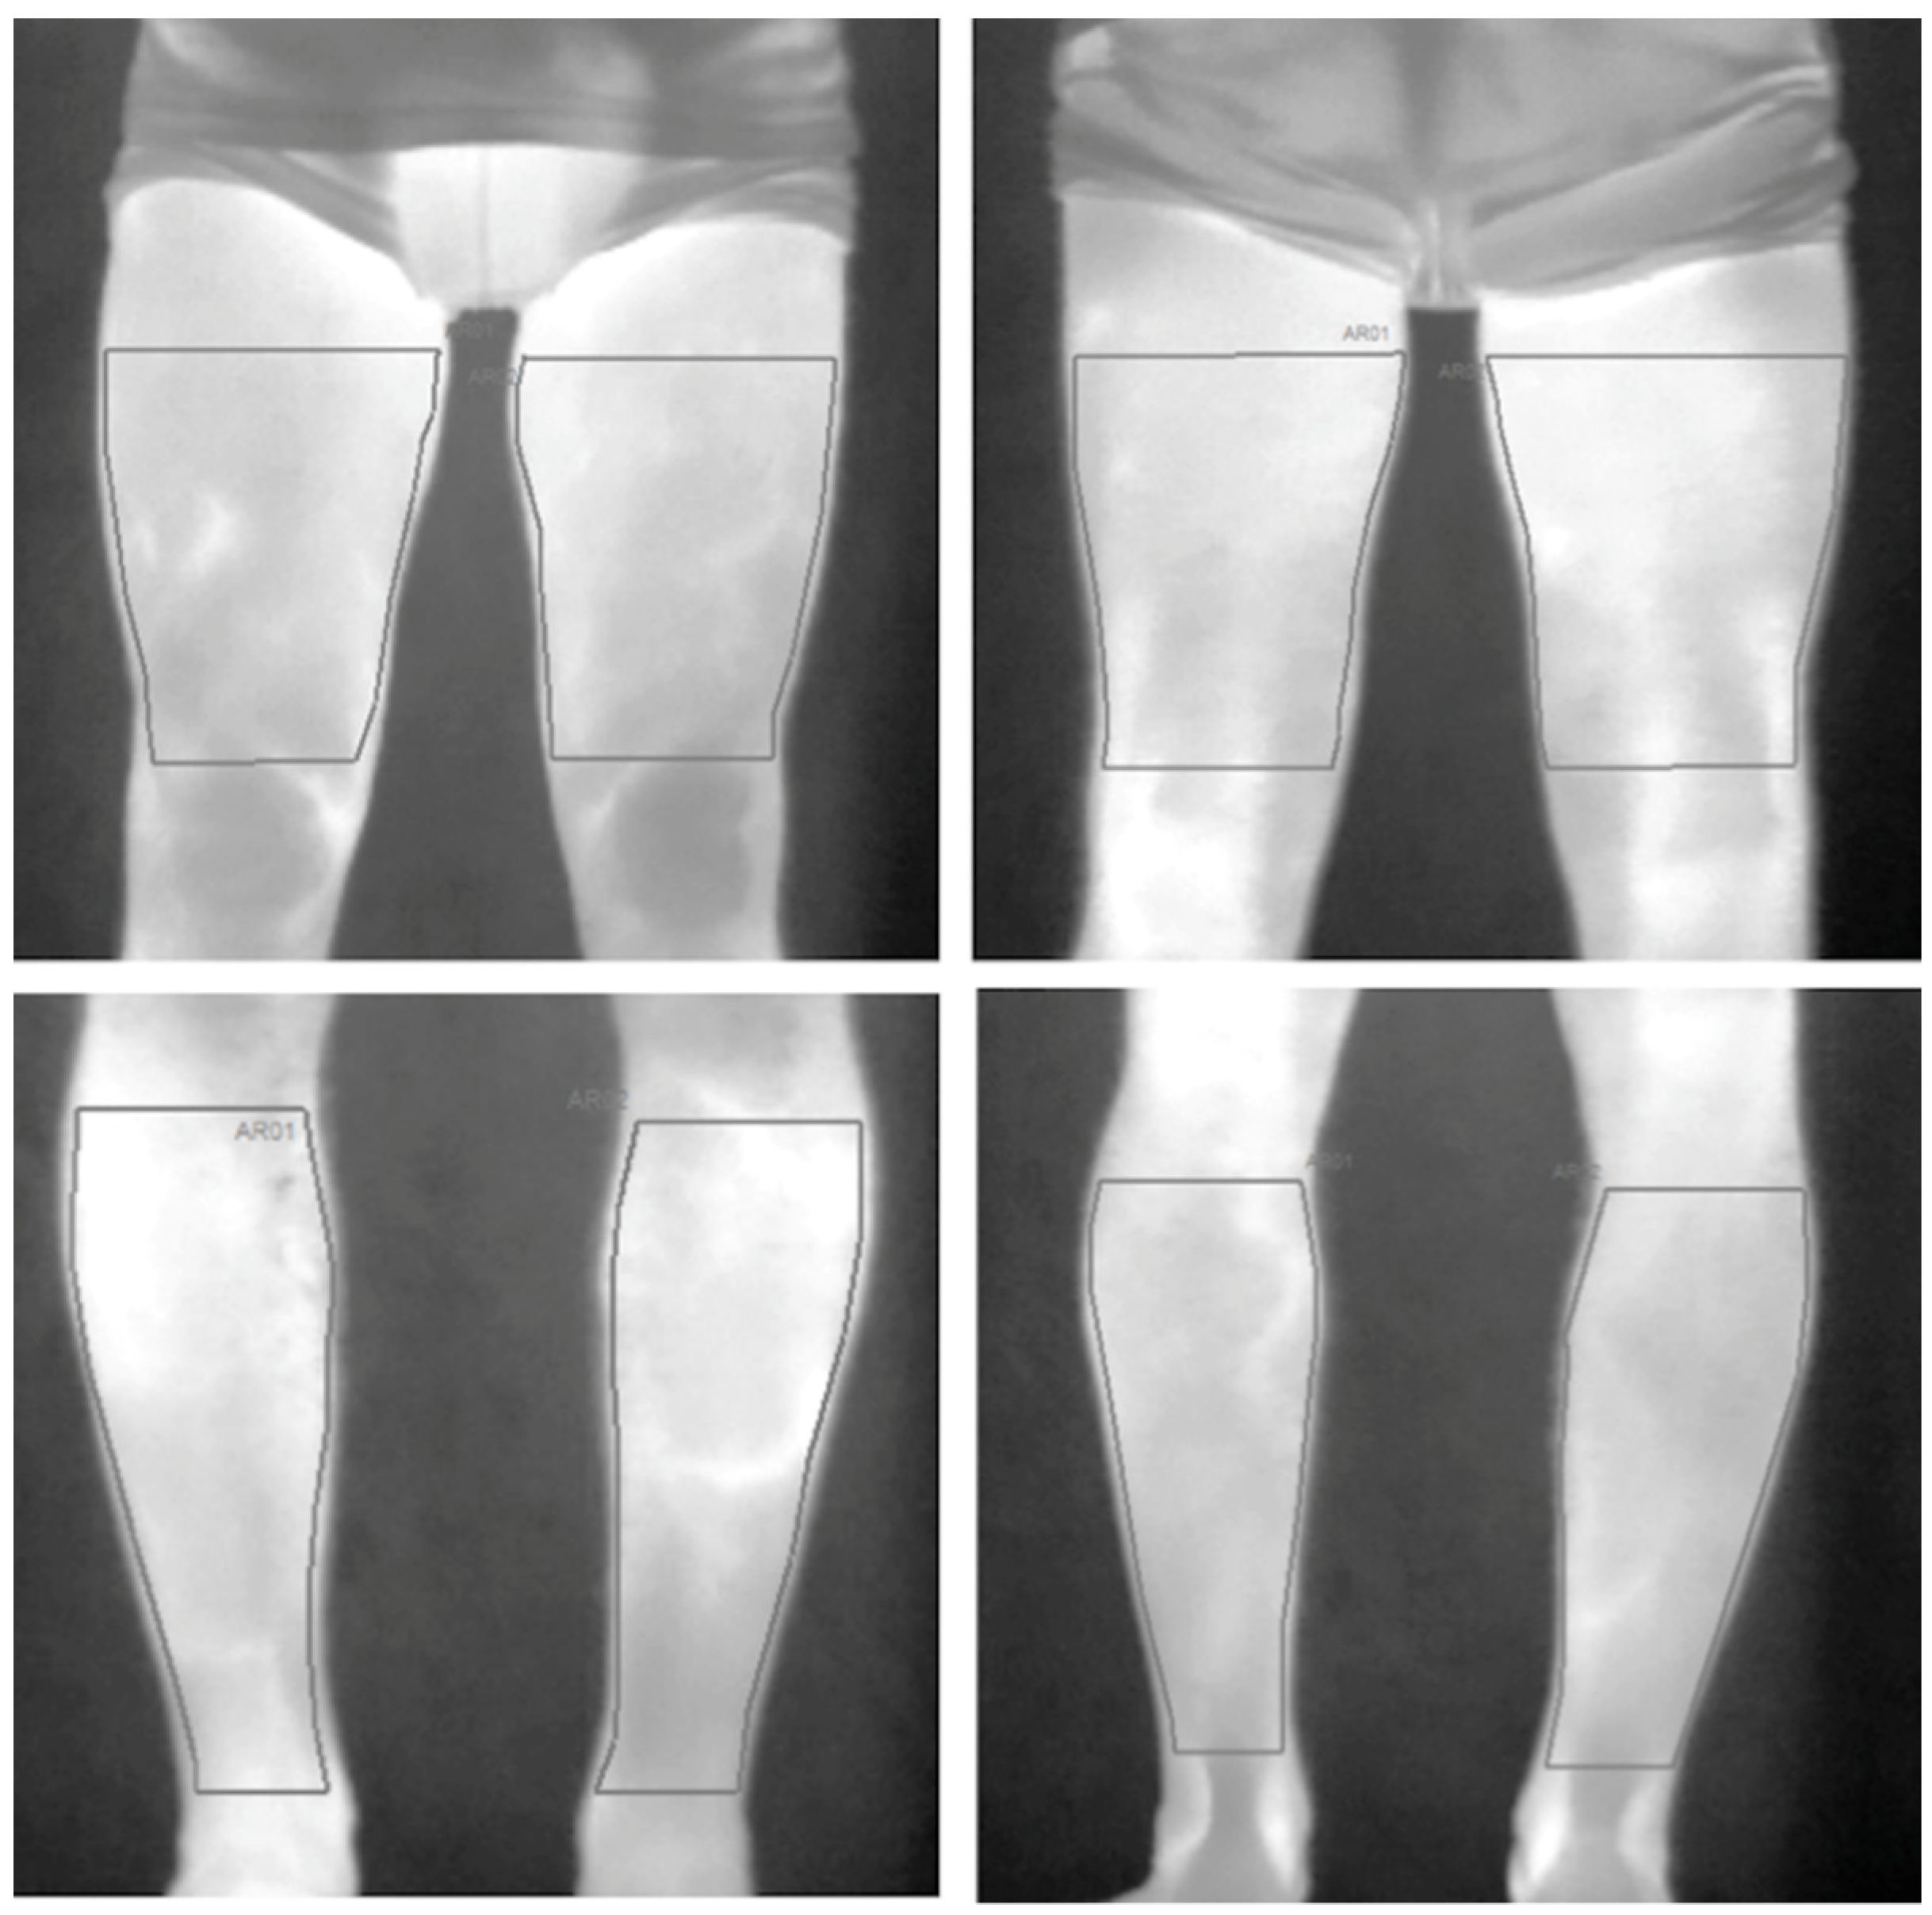

2.6. Skin Temperature